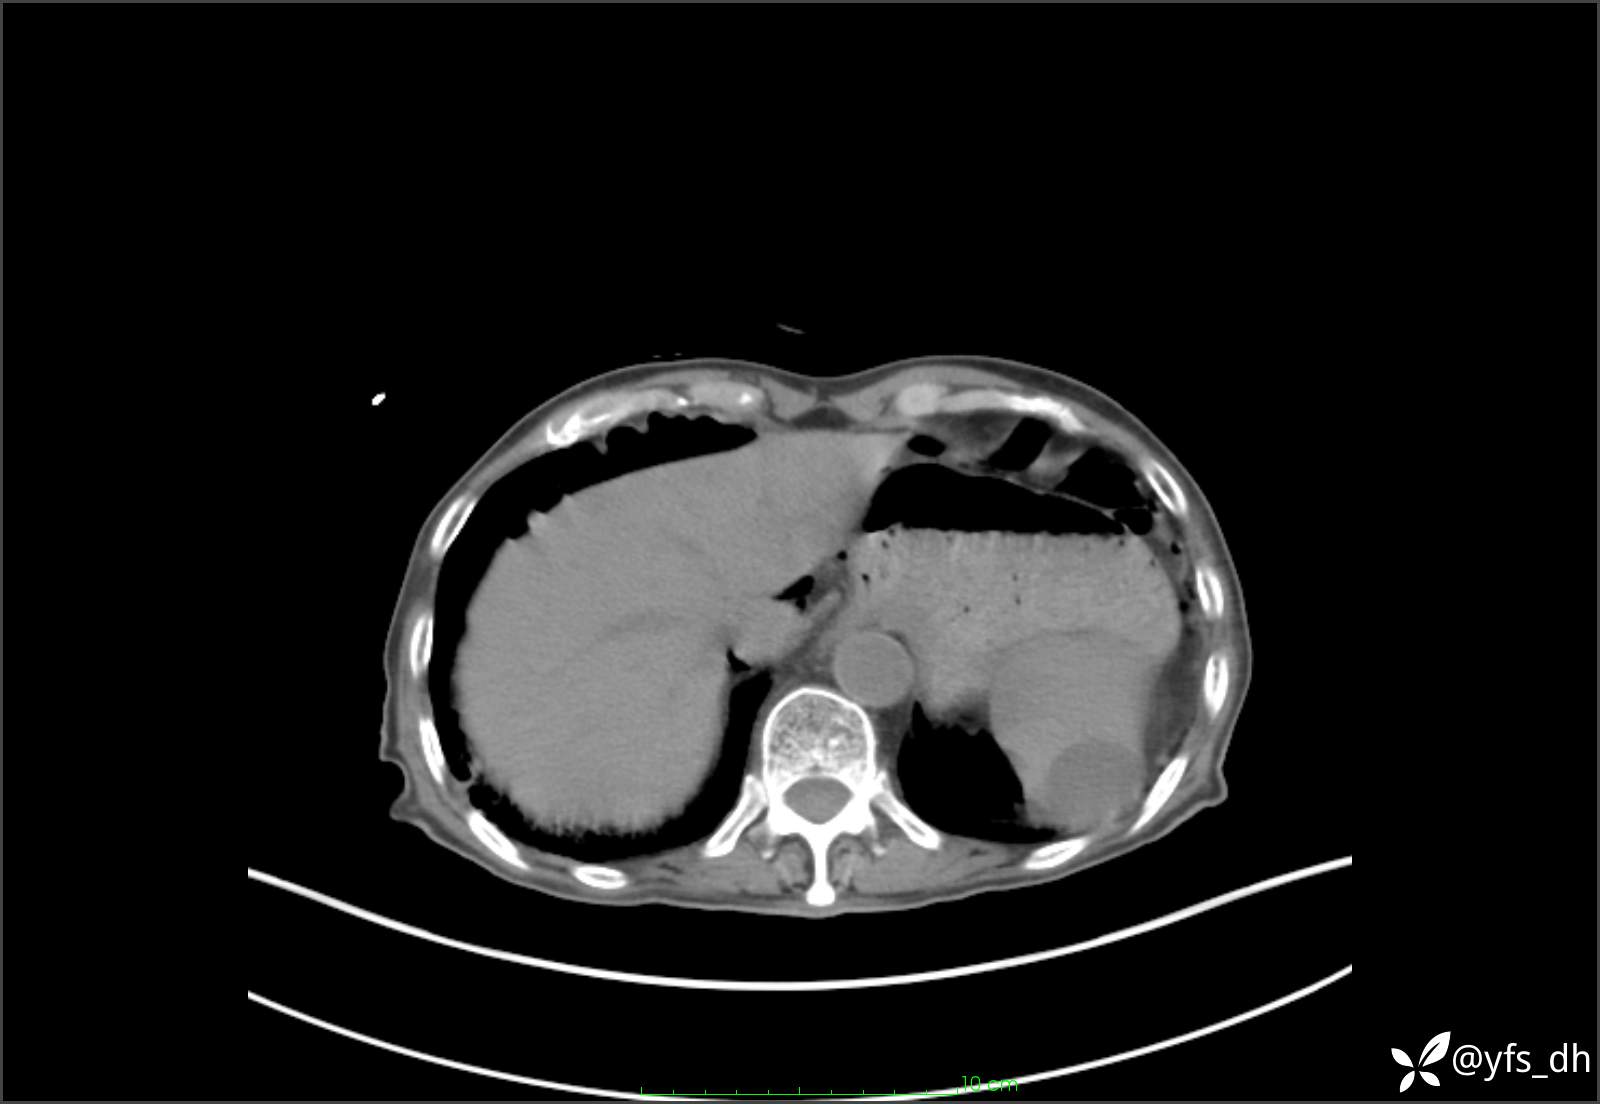

1.简要病史:患者4天前突发上腹部疼痛不适,但可以忍受。3小时前饭后突然加重,不能忍受后就诊。

2.简要手术记录:术中见腹盆腔大量肠液及粪便,乙状结肠中下段见一约3cm的破口。